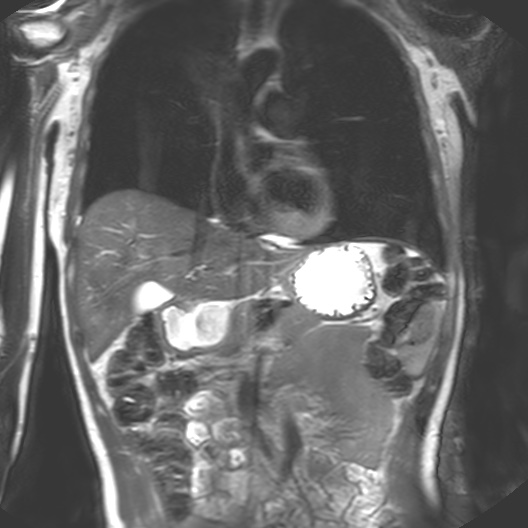

I began my investigation by taking part in MRI trials at the Cancer Centre in 2018 with Dr Heather Fitzke. MRI images confront us with the fact that our bodily materiality acts beyond us and that medical technology shapes our sense of self.

Seeing my organs autonomously pulsing on the monitor in the control room had a pronounced impact on me. It was like looking into a rockpool within my own body. The affecting power of MRI (its power to change our emotions) is in its potential to reveal autonomic bodily functions and diseases which are beyond our control. The data on the screen revealed my autonomous self: peristalsis, bowel movements, digestion, heartbeats and respiration. Through MRI, anatomy is seen as embedded and relational.

I felt a deep sense of fascination with how my organs moved and worked. Haraway’s situated biopolitics argues for an account of the body as an environment, in a state of simultaneous dissolution and formation which I notice in my data. My organs seemed like invertebrates in a rockpool: a squishy pulsing ecosystem. Organs do not operate in isolation but are interconnected. Their autonomous pulsing and motion seemed creaturely and strange in contrast to my numerous encounters with preserved cadavers in the dissecting room. My organs keep me alive yet I have no conscious sense of their functioning. They function beyond me.

Selecting the correct materials to make phantoms was the first step in interacting with the body-machine (interface). I would refer back to my data sculpture and cross-sectional projections from my scans with Dr Fitzke.

Anatomy as a rockpool